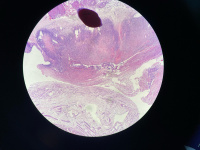

卵巢非典型内膜异位?

性别

女

年龄

49

临床诊断

子宫肌瘤

一般病史

无

标本名称

全子宫双附件

大体所见

附件未见特殊

病灶就这些,请教诊断

图1

像子宫内膜异位